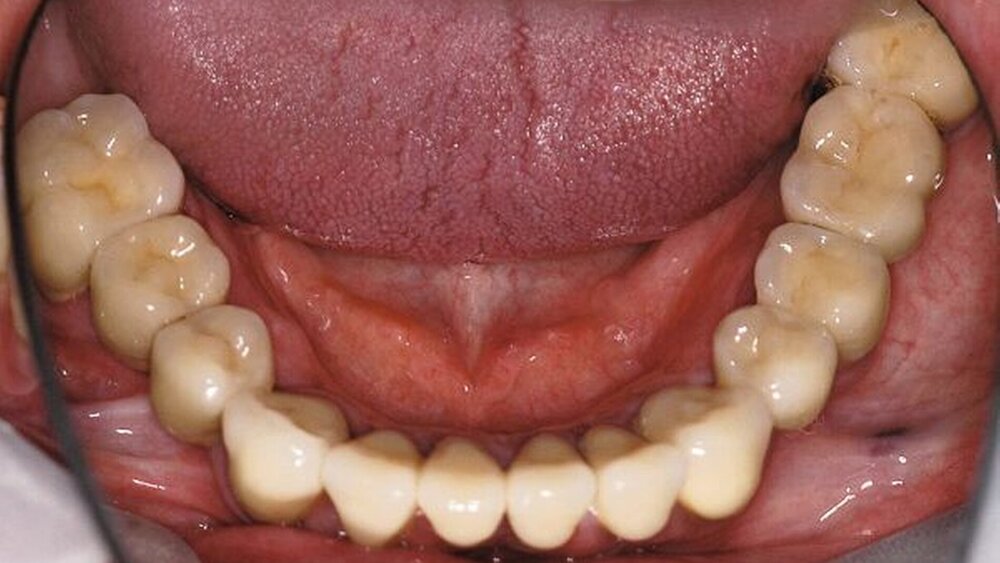

Im Rahmen der intraoralen Befunderhebung wurde festgestellt, dass die Gingiva insgesamt gerötet und ödematös war. Die Messung der Taschentiefe ergab einen durchschnittlichen Wert von fünf mm. Der ermittelte PSI (in Bezug auf die Sechstanten) ergab die Werte 4, 2, 4, 3, 2, 2. Pusaustritt konnte in regio 17 und in regio 27 festgestellt werden, so dass der Erhalt dieser Zähne fraglich war. Im Oberkiefer lag ein prothetisch versorgtes Lückengebiss der Kennedy-Klasse III2 vor. Die Zähne 18, 16, 15, 11, 25, 26 und 28 fehlten. Die prothetische Versorgung bestand aus einer Brücke 17 bis 14 zum Ersatz von 16 und 15, einer Brücke 13 bis 23 zum Ersatz von 11 und einer Brücke 24 bis 27 zum Ersatz von 25 und 26. Sämtliche Brückenanker wiesen Randundichtigkeiten und Sekundärkariesbildung auf. An 21 konnte eine großflächige Keramikabplatzung festgestellt werden. 17 und 27 reagierten im Perkussionstest stark positiv. Im Rahmen einer Sensibilitätsprüfung mittels CO2-Schnee reagierten die Zähne 17, 22 und 27 negativ. Im Unterkiefer lag ein Gebiss der Kennedy-Klasse II3 vor. Die Zähne 38, 36, 34, 44, 45, 47 und 48 fehlten. Die Zähne 37, 42, 46 waren mit Füllungen versorgt, die erhebliche Undichtigkeiten aufwiesen. 46 reagierte im Kältetest negativ. Alle Unterkieferzähne wiesen starke Attritionen auf. Diese Zähne 33 bis 43 sowie 37 und 35 reagierten im Kältetest stark schmerzhaft (Abbildungen 4, 5).